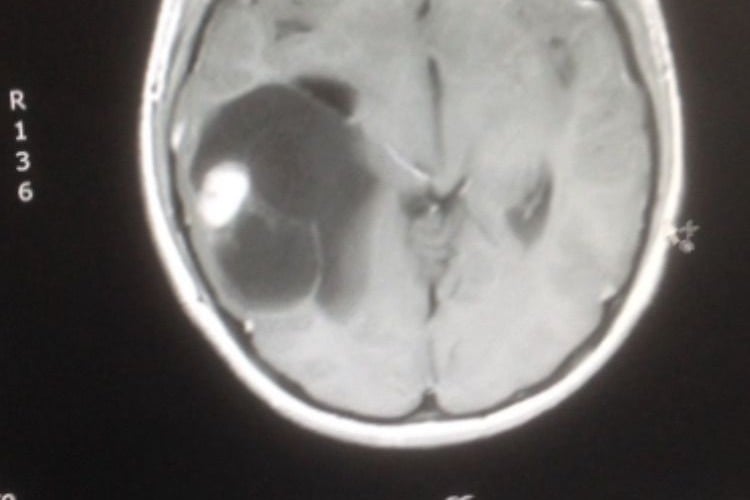

It was only when a paediatric doctor requested an MRI scan that the truth was discovered, a parietal pleomorphic xanthoastrocytoma, a decision Llyr’s mother, Gaenore Evans, believes saved her son’s life.